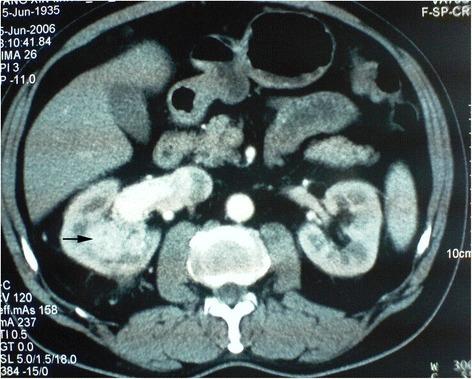

A total of 32 BSSRCC patients, including 28 males and 4 females, were enrolled the study from January 2004 to May 2016. The diagnoses were defined by the measurements of CT, ultrasound, and MRI. Patients with hereditary syndrome were excluded. The management of surgical manner, operation staging, and sequence were scheduled in accordance with the tumor's location and size (based on Zhongshan score, ZS score), as well as the performance status of the patients. Among them, 8 cases were conducted with bilateral surgical procedure simultaneously and 24 cases were implemented with staged operations. NSS on the one side with contralateral RN, and NSS on both sides were performed in 17 and 15 patients separately.

2004年1月至2016年5月,共纳入32例BSSRCC患者,其中男性28例,女性4例。通过CT、超声和MRI测量进行诊断。排除患有遗传性综合征的患者。根据肿瘤的位置和大小(基于中山评分,ZS评分)以及患者的体能状态安排手术方式、手术分期和顺序。其中,8例同时进行双侧手术,24例进行分期手术。17例患者行一侧保留肾单位手术(NSS)并对侧肾切除术(RN),15例患者行双侧NSS。